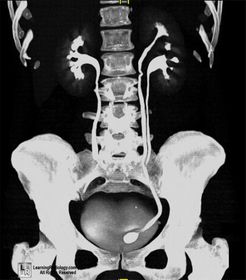

Hydronephrosis Water in the nephrons of the kidney (there is no actual water though) Results from an obstruction of the renal pelvis, calyces, and ureter due to back pressure of urine that can't flow pas the obstruction Is NOT an actual disease but results from another Occurs bilaterally in pregnancy due to fetus pushing against ureters Symptoms: hematuria, pyuria, flank pain, fever Radiographic Appearance: IVU-enlargement above the obstruction and no anatomy demonstrated below, calyces are sharp in appearance with enlargement